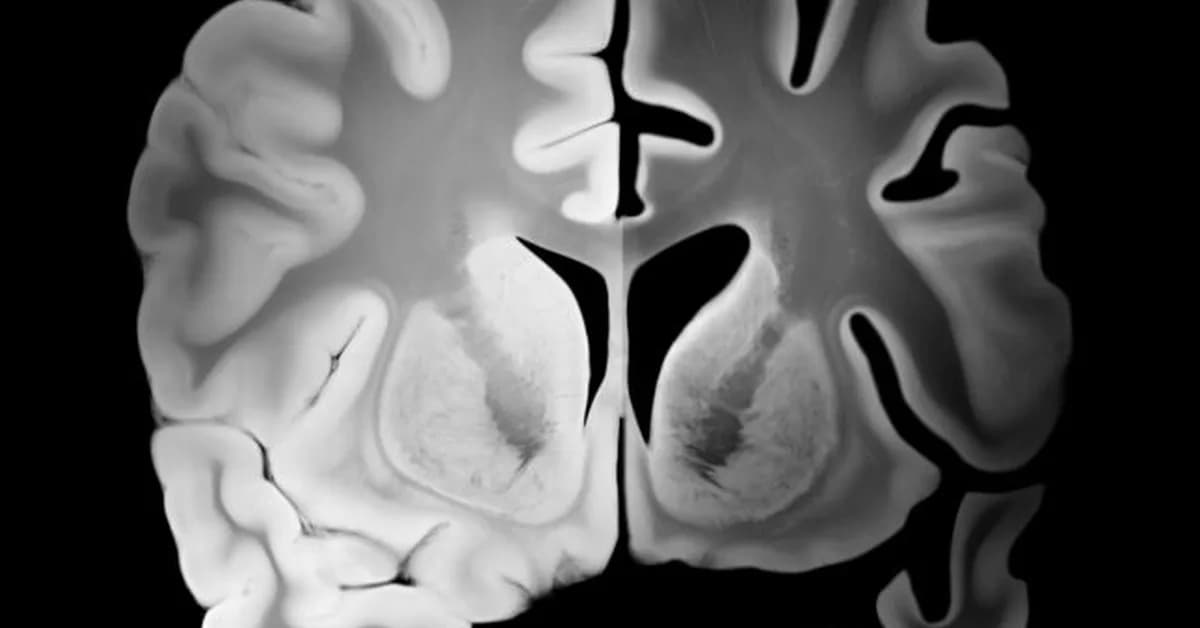

Governments and industries are investing heavily in neuroscience to combat brain diseases and promote cognitive health, emulating successful cancer and heart health frameworks. However, this focus often overlooks mental illness, creating a strategic error by treating it as secondary rather than integral to overall brain health. This divide could hinder comprehensive advancements in neurological care and should be addressed in future research initiatives.